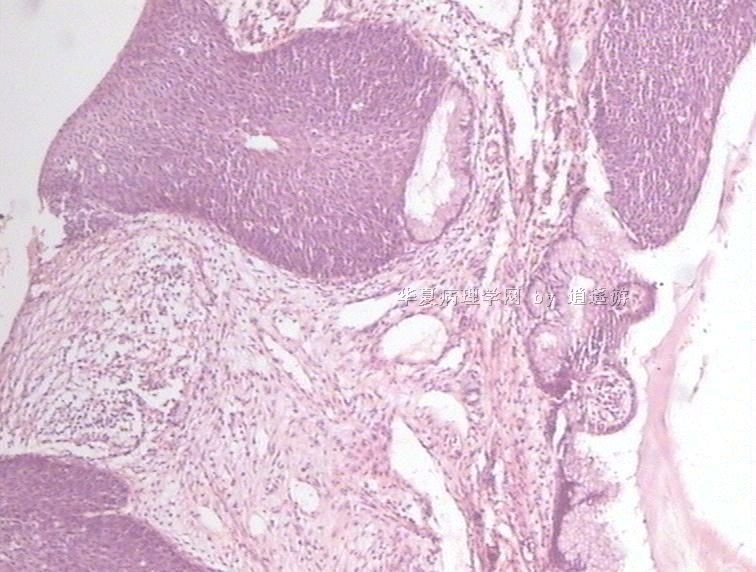

姓    名: ××× 性别:  女 年龄:  40

标本名称:  宫颈leep环切术切除组织

简要病史:  宫颈Ⅲ度糜烂

图1、2,10×,图3-6,4×,图7、8,40×

设备不够好,图像较模糊。

CIN3级累腺。

多看看是否有浸润,以及切缘。

CIN3级累腺,切缘是否干净?

CIN3级累腺

未见到浸润,但边缘看起来未切净。

同意.

很典型的.